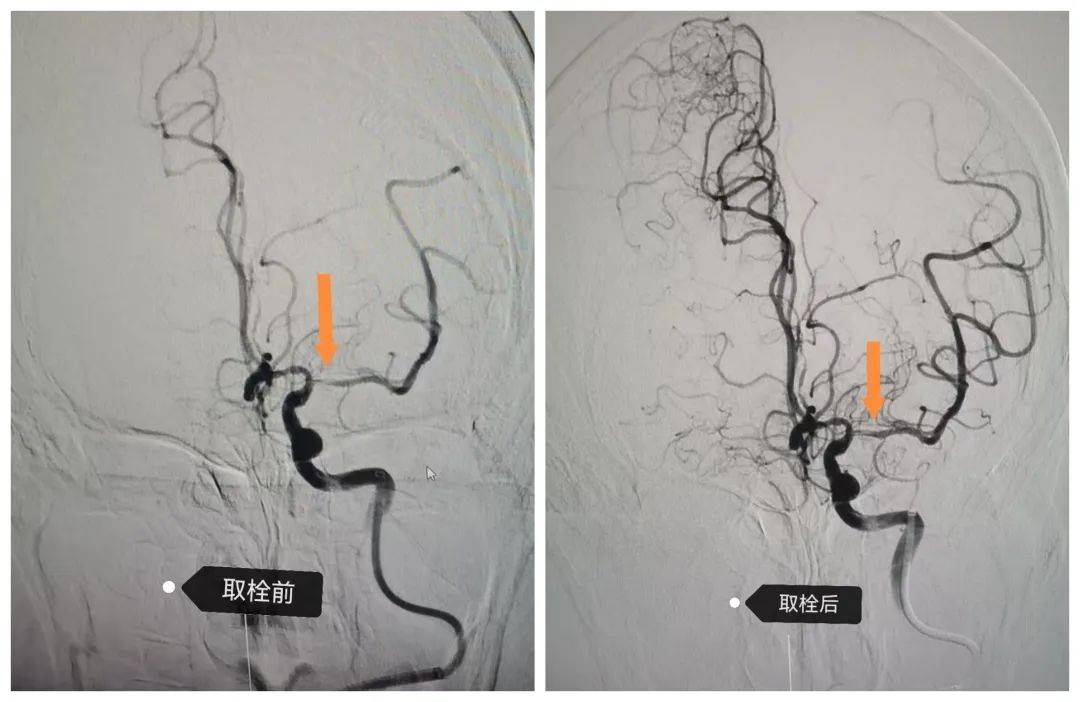

55歲的袁大姐以“突發(fā)頭暈伴嘔吐 4 小時”入院,既往高血壓病史,入院時嗜睡、雙側(cè)瞳孔不等大,頭顱核磁顯示雙側(cè)小腦、左側(cè)丘腦及右側(cè)頂葉多發(fā)急性梗塞,基底動脈閉塞,病情危急??浦魅卧闱俾?lián)合介入醫(yī)師王文新緊急制定方案,急診“主動脈弓造影 + 全腦血管造影 + 腦動脈取栓術(shù)”。術(shù)后患者神志轉(zhuǎn)清,言語功能顯著恢復,出院時肢體肌力明顯改善,需繼續(xù)康復鍛煉。